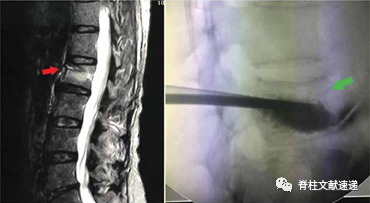

图注:压缩的骨小梁会在局部形成硬化层(左,红色箭头),这会影响PVP术中水泥的分散(右,绿色箭头);

图注:MRI压脂像结果显示患者术前合并腰背部筋膜损伤